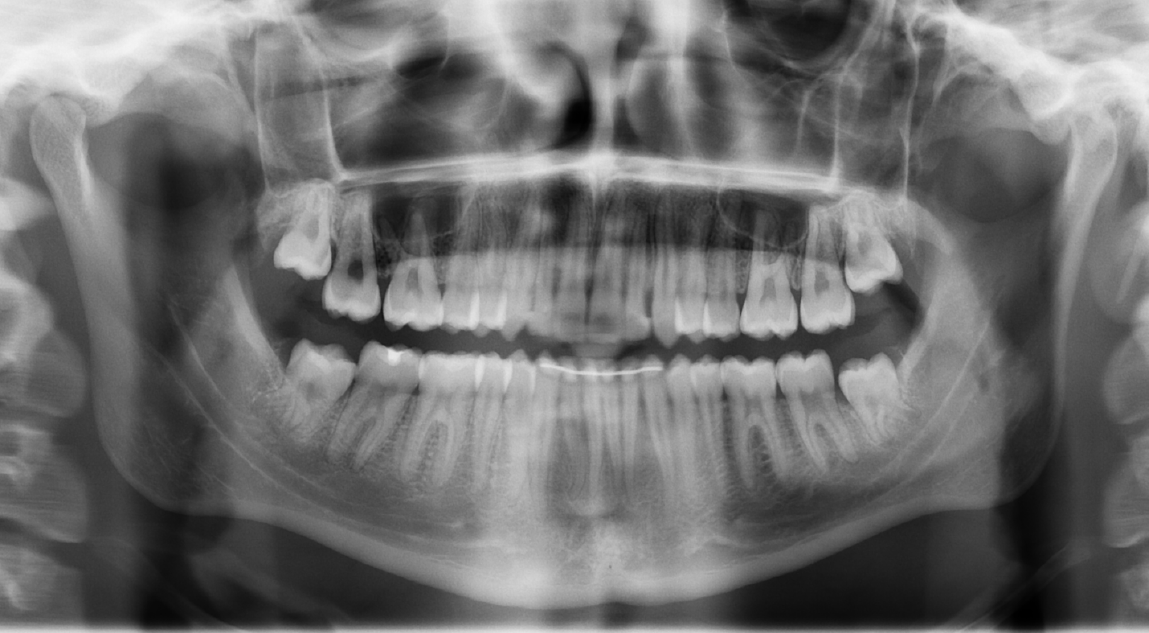

Figure 3 Pre-treatment panoramic radiograph examination.

A: Panoramic radiograph shows the presence of ectopic maxillary canines; B: Assessment of maxillary canines' positions shows an average to good prognosis.